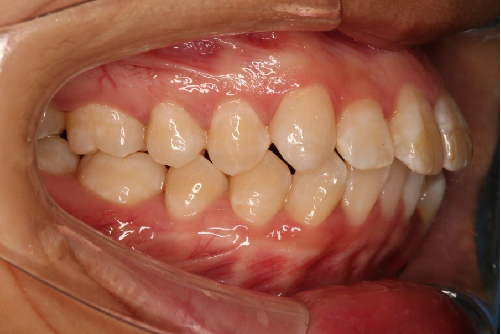

• 磨牙,尖牙I类关系,中线齐

• 上下牙列中度拥挤

• 上下前牙唇倾

IntraoralExamination(2016-08.31,Wu)